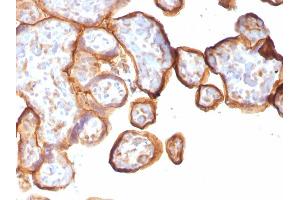

THBD 适用: 人 IHC 宿主: 小鼠 Monoclonal 141M unconjugated Recombinant Antibody

产品编号 ABIN7826102

100 μL (More quantities available)